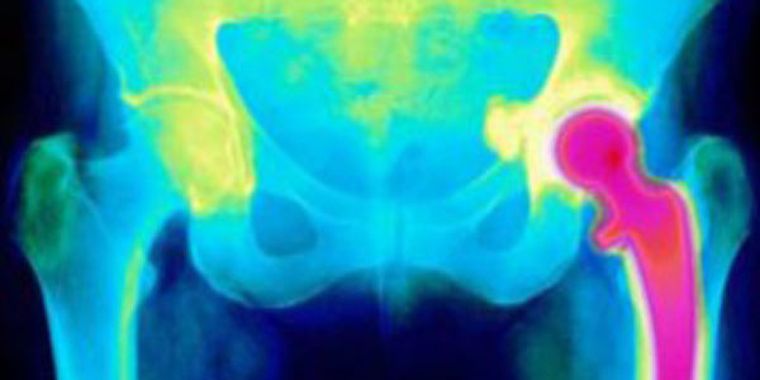

Un equipo de biólogos, nanoingenieros y cirujanos diseñó una nueva técnica para poder contar con un reemplazo de cadera que puede durar toda la vida del paciente.

Los científicos británicos cubrieron la prótesis con un "nanopatrón" de plástico perforado para estimular a las células madre a formar nuevo hueso junto a la nueva articulación.

El procedimiento intenta evitar los problemas que surgen actualmente cuando el organismo forma tejido blando alrededor de las prótesis de reemplazo de cadera.